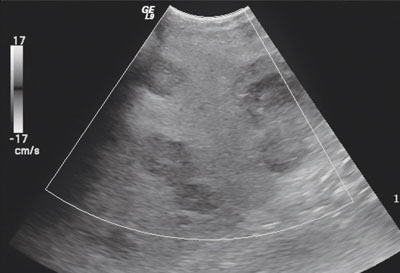

الموجات فوق الصوتية والأشعة المقطعية

في حالة شك الطبيب في وجود سرطان البنكرياس، فإن هناك عددا من الفحوص والتحاليل، التي تشمل اختبارات الدم للكشف عن دلالات الأورام، إضافة إلى الموجات فوق الصوتية، والأشعة المقطعية واللتان تشكلان الدعامة الأساسية؛ للتعرف على سرطان البنكرياس وتحديد مدى تقدم حالة الورم.